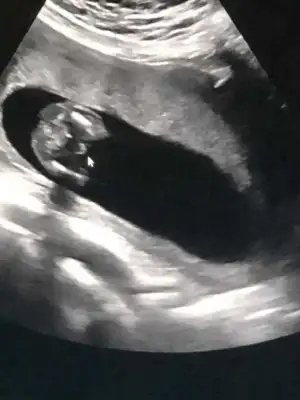

Çok uzun olmuş ama benim ki ne ozaman

• 3303A396-9749-4F92-931E-7600EC1683D2.webp

3303A396-9749-4F92-931E-7600EC1683D2.webp

27,2 KB · Görüntüleme: 366